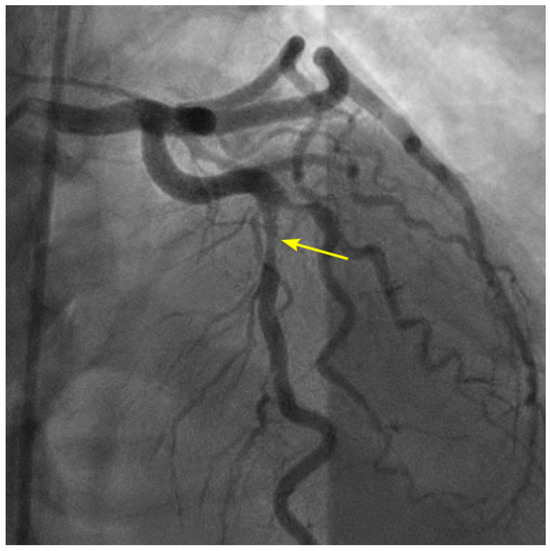

Figure 14.

(A,B) Recirculating flow due to blood converging from two branches in the retrograde direction. (A) Coronary angiogram of an elderly patient with a severe lesion proximal to the bifurcation of the distal right coronary artery (RCA) and the posterior descending artery (arrow). (B) The blood converges from a large main branch and one smaller side branch (The yellow arrows point to the retrograde direction of the blood flow). Because of differences in velocity, the flow at the inner curve recirculates and starts a slow atherosclerotic process [10].